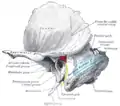

Dural veins. (Transverse sinuses labeled as "SIN. TRANS." at center right.) | |

The transverse sinuses (left and right lateral sinuses), within the human head, are two areas beneath the brain which allow blood to drain from the back of the head. They run laterally in a groove along the interior surface of the occipital bone. They drain from the confluence of sinuses (by the internal occipital protuberance) to the sigmoid sinuses, which ultimately connect to the internal jugular vein. See diagram (at right): labeled under the brain as "SIN. TRANS." (for Latin: sinus transversus).

Dura mater and its processes exposed by removing part of the right half of the skull, and the brain The sinuses at the base of the skull